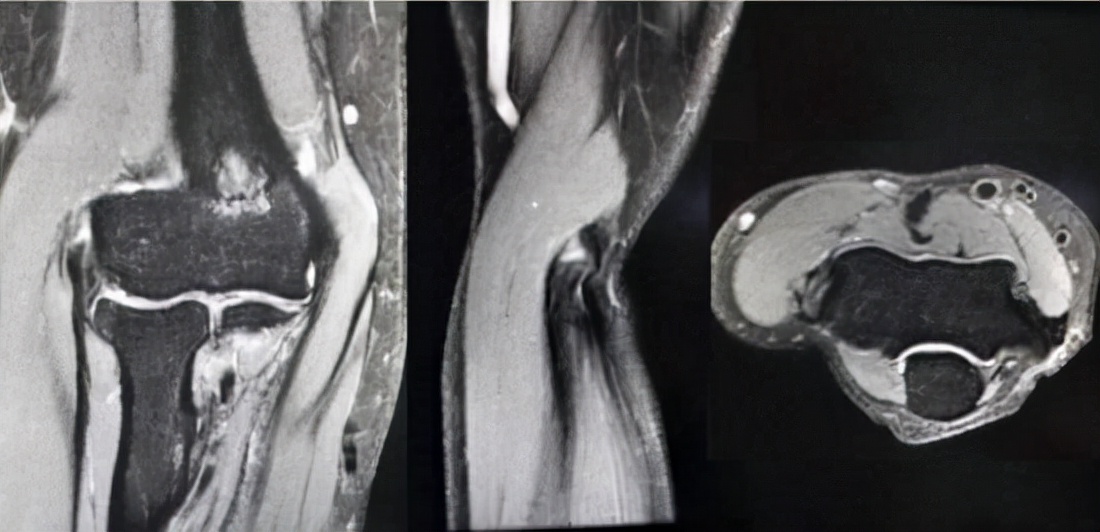

网球肘手术治疗的方式 根据组织退变程度及位置(通过影像学检查进行判断)的不同,网球肘的手术治疗有关节镜下的微创手术和传统开放性手术(创口很小)两种选择。无论是关节镜下的微创手术还是开放性手术,主要目的是肌腱的清创和修复:将变性的、不良的肌腱组织清除,然后将其与邻近的肌腱组织缝合固定,帮助肌腱自我修复。

网球肘手术治疗的适应证 1、经非手术治疗后,经常复发、且对工作和运动造成严重影响的。2、慢性、顽固性网球肘,经过正规保守治疗6-12个月后无效的。3、存在大范围难以消除的钙化、纤维化。4、上述情况下,如果不实施手术治疗,问题只会逐步恶化,引发严重的手、腕及前臂功能退化。